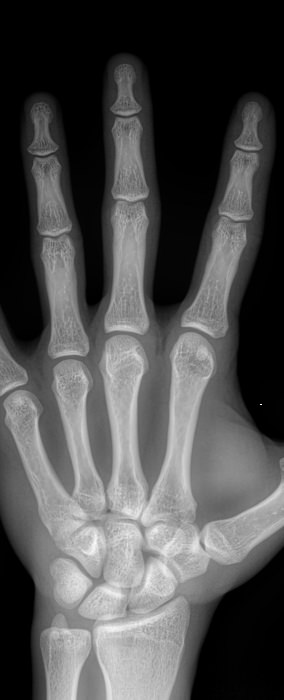

Все изменения хорошо видны на рентгеновском снимке, он и будет первым, а чаще и основным, видом диагностики. Основываясь на рентгенограмме, а также лабораторных показателях, врач выбирает оптимальное лечение и дальнейшее ведение болезни.

На прицельном снимке будут отчетливо видны следующие изменения:

• Суставная щель может быть расширена, в том числе неравномерно, или сужена, в ней обнаруживается выпот или участки обызвествления;

• Суставные поверхности могут не соответствовать друг другу из-за вывиха;

• В тканях кости и надкостницы обнаруживаются участки разрежения, уплотнения, разрастания, воспаления, перелома;

• Утолщение мягких тканей;

• Новообразования, при наличии.